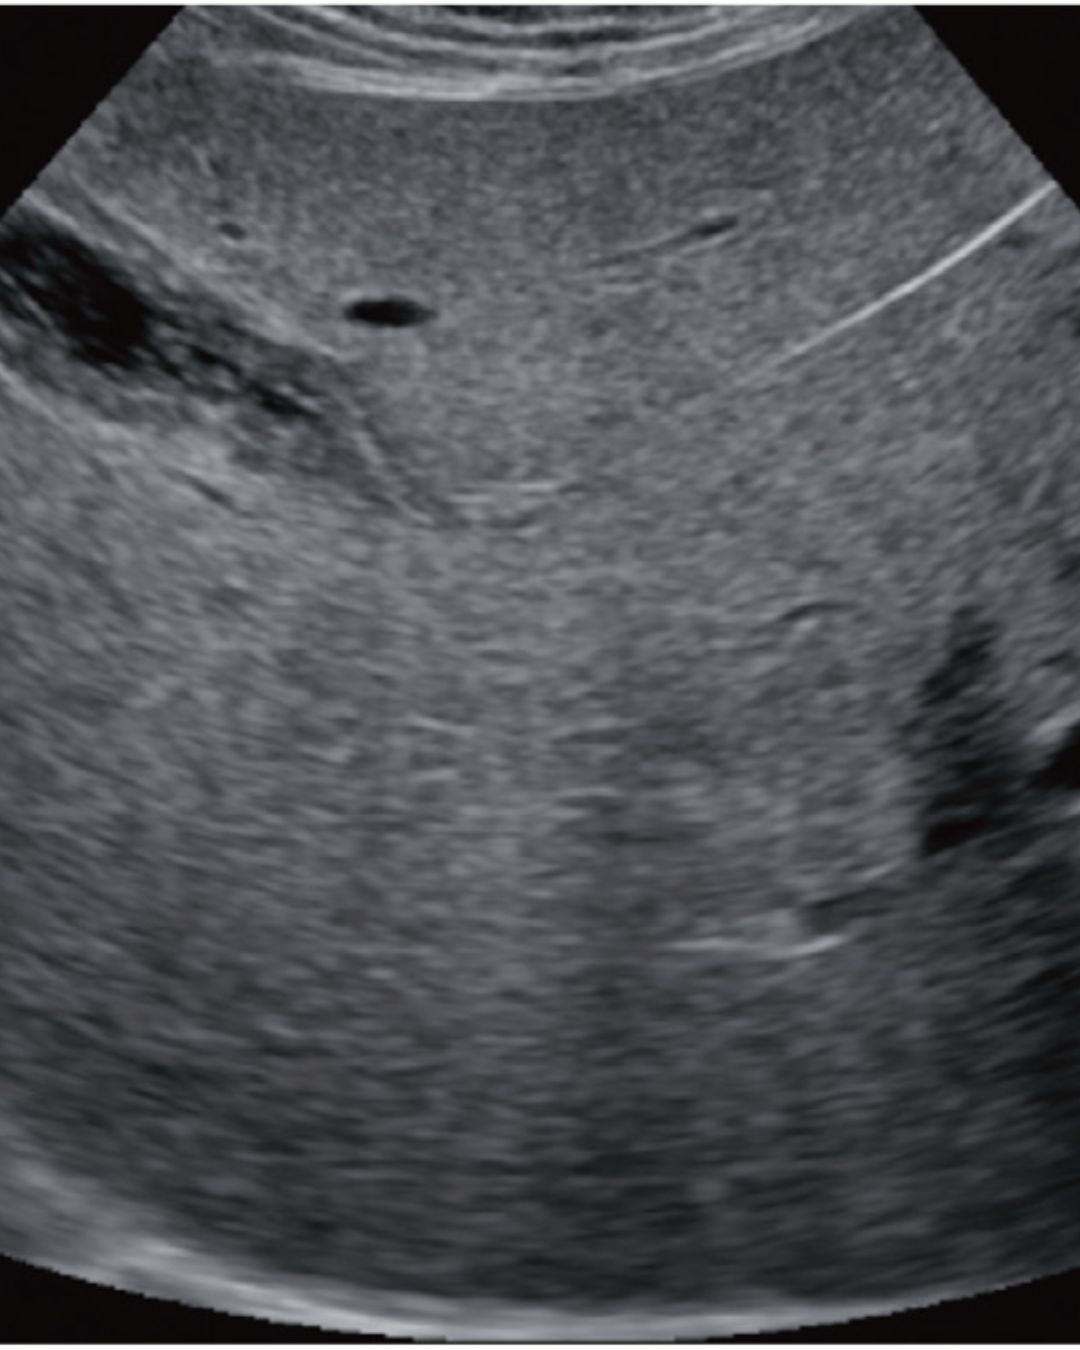

УЗД печінки та жовчного міхура